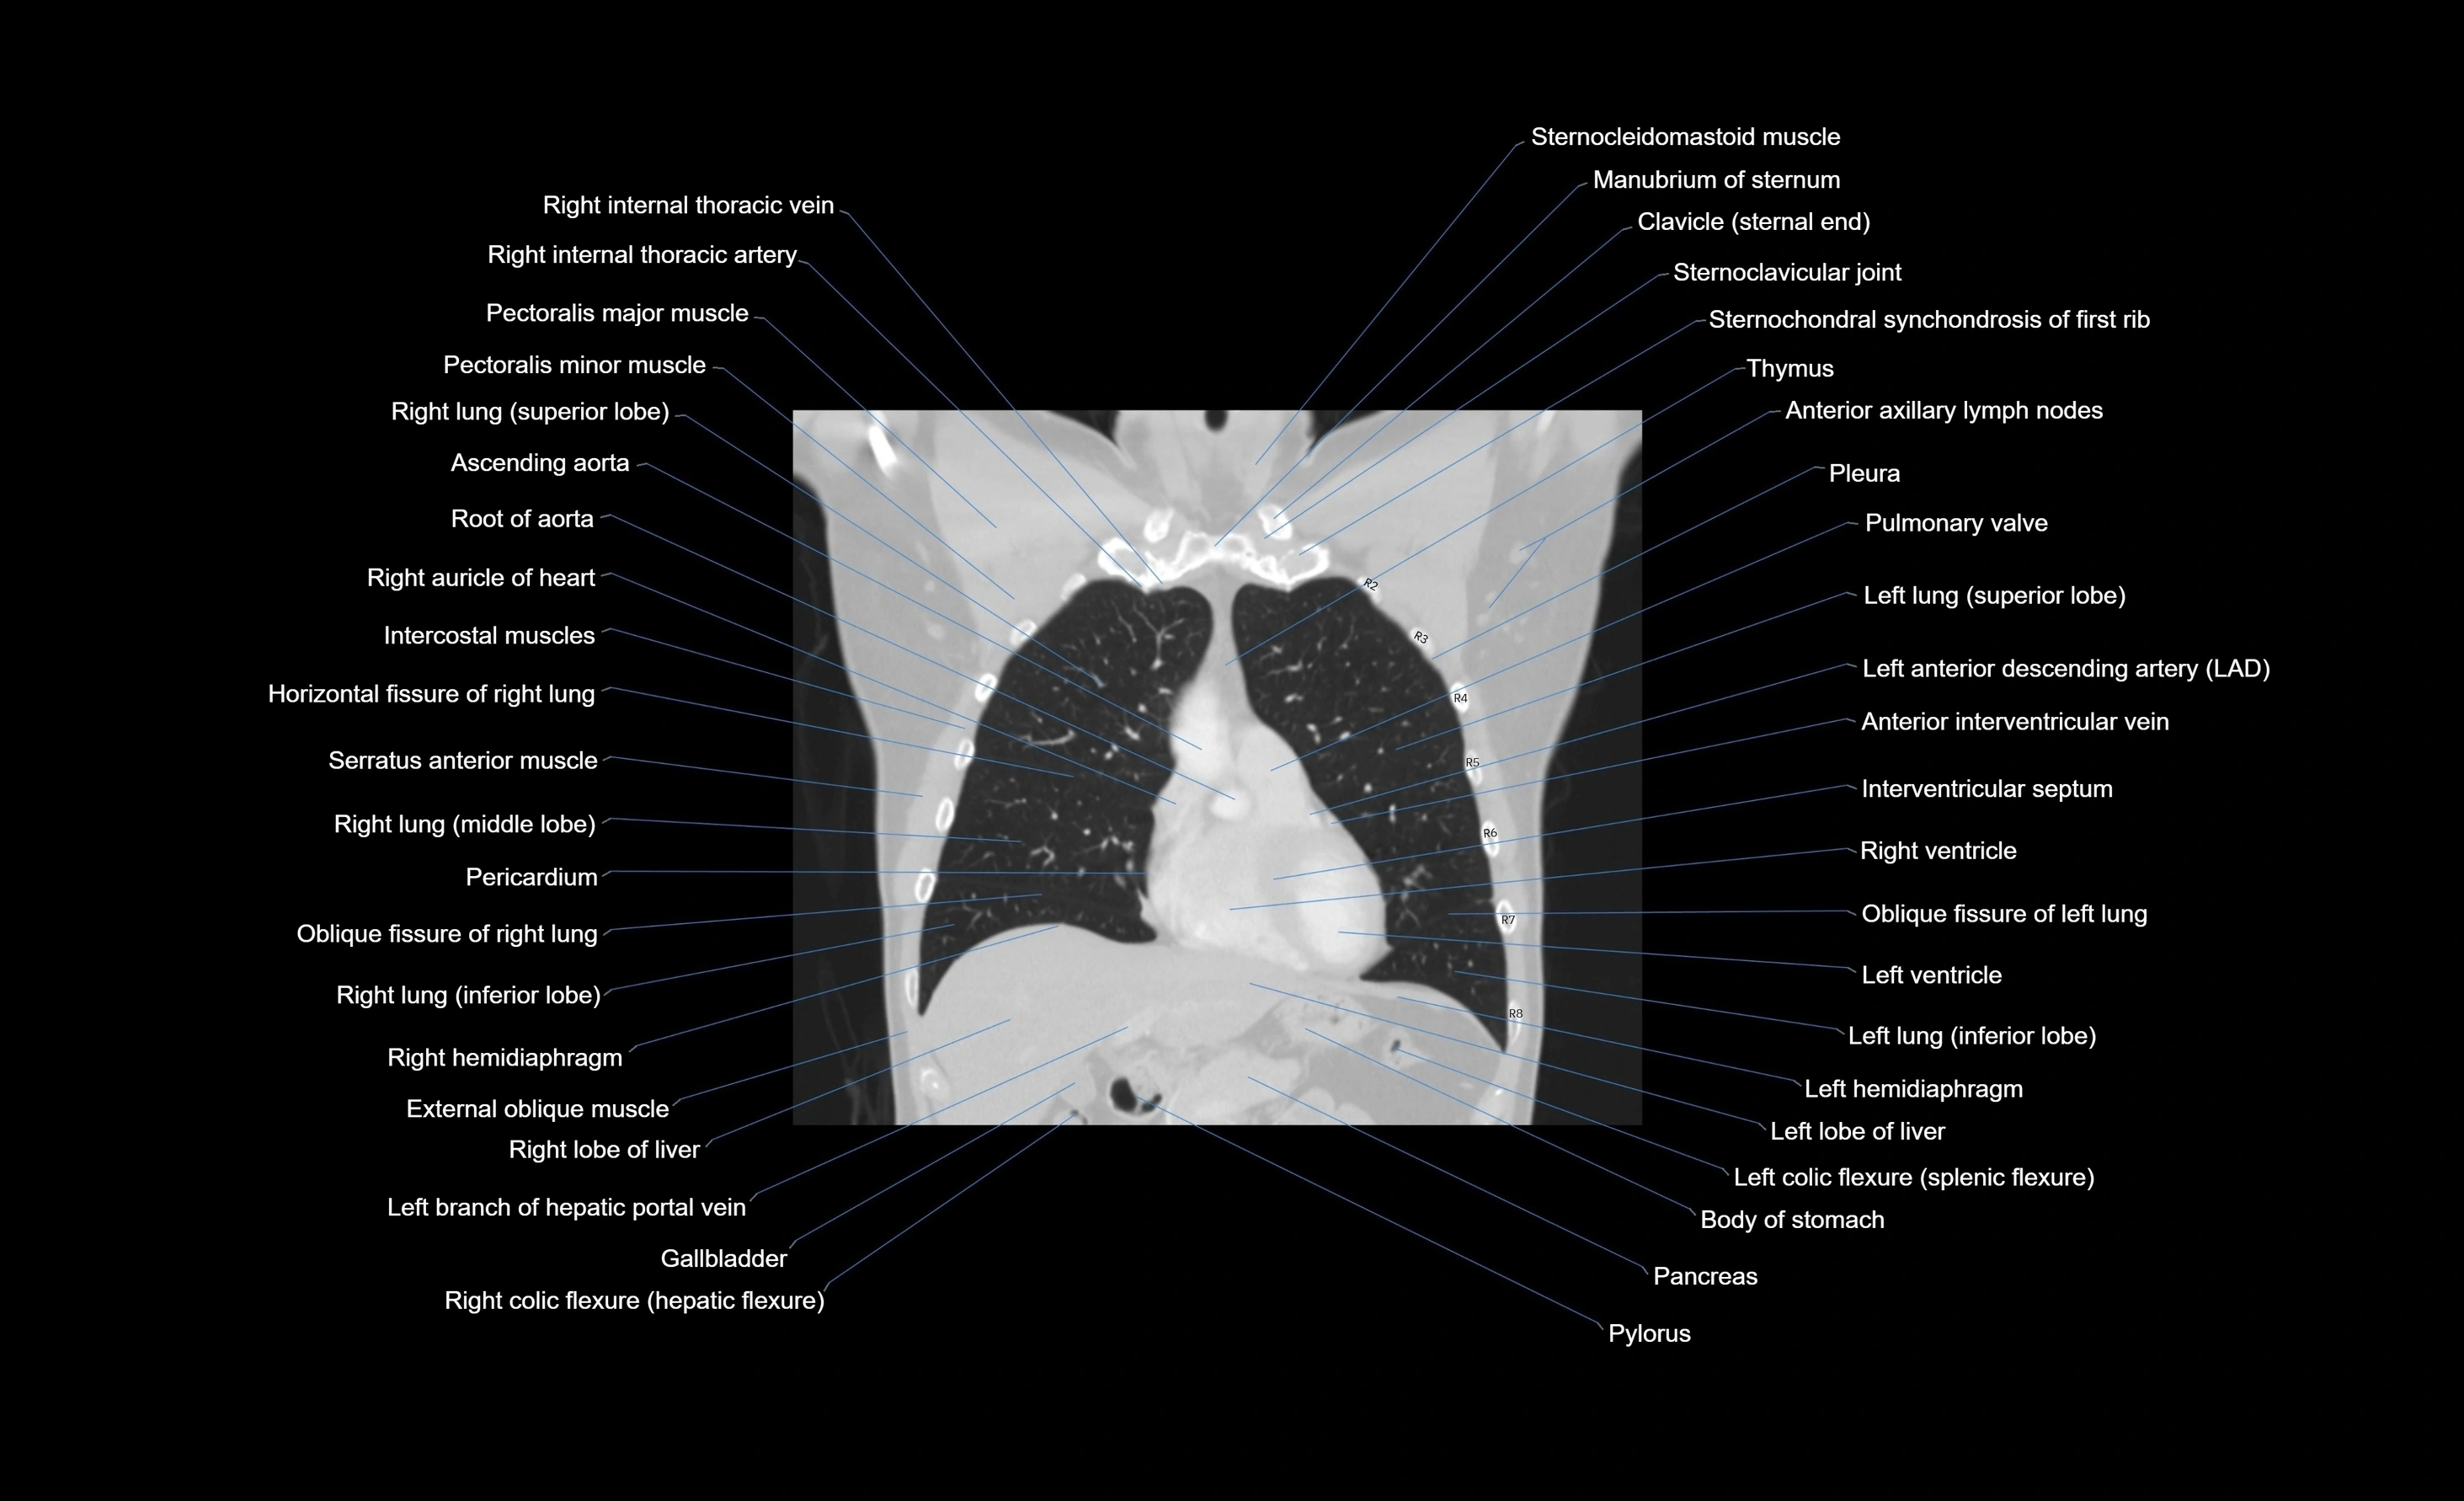

CT images